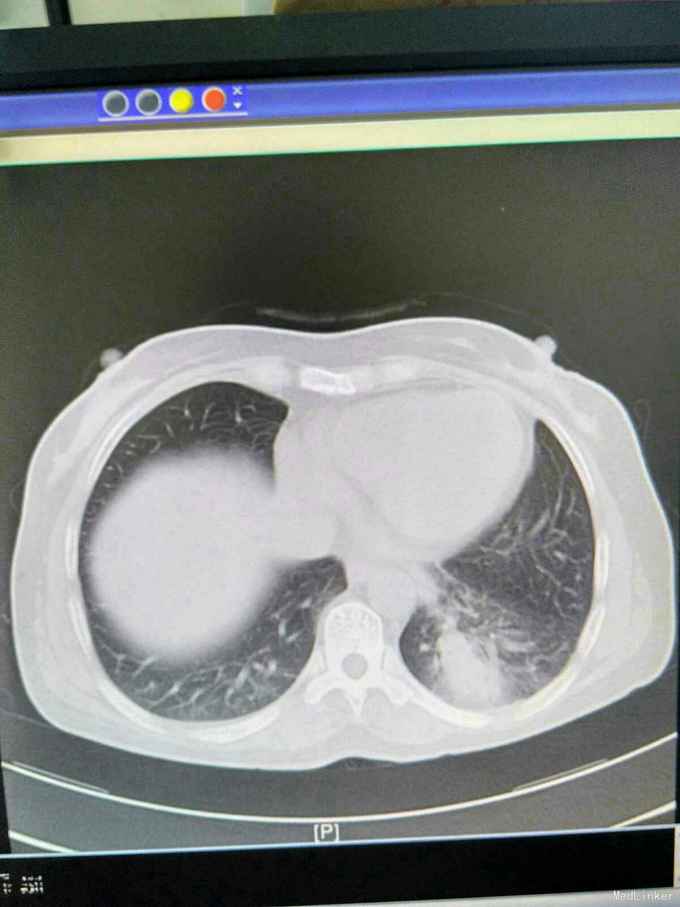

患者44岁女性,以“咳嗽咳痰间断咯血1月余”为主诉入院,入院前1月余不明显诱因出现咳嗽,呈阵发性非刺激性,咳黄白痰,每日五六口,间断咯血,色鲜红,每次10到50毫升不等,余无特殊不适,就诊当地医院摄胸部ct提示左下肺炎,予抗感染止咳化痰止血处理后症状反复,半月前复查胸部CT提示肺部阴影较前增大。

查体,神志清楚,浅表淋巴结未触及肿大,左下肺呼吸音减弱,可闻及少许湿性啰音。外院胸片示,左下肺斑片状实变阴影。

我院胸部ct增强,见左下肺病灶内见一异常供血血管,发自降主动脉,病灶周围见斑片状磨玻璃影。诊断为左肺下叶肺隔离症,转外科治疗。